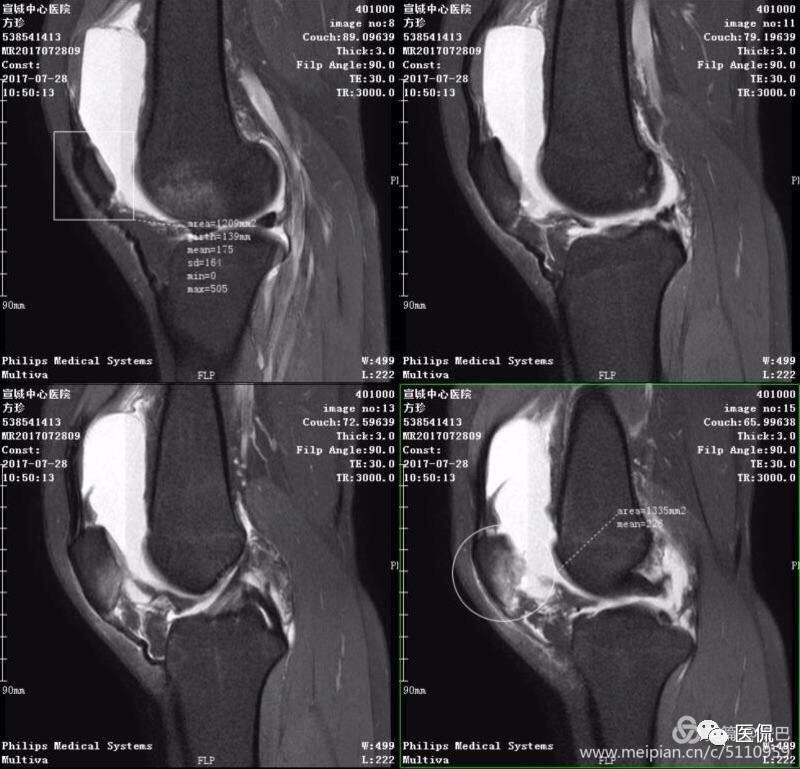

1、单液-液平面:上层呈短T1、长T2信号、T2压脂像低信号、Pd像呈高信号;下层呈中等T1、T2信号、T2压脂像和Pd像呈较高信号。

2、双夜-液平面:上层呈短T1、长T2高信号、T2压脂像低信号、Pd像呈高信号;中层呈长T1、长T2信号、T2压脂像和Pd像呈较高信号;下层呈中等T1、T2信号、T2压脂像和Pd像呈较高信号。

3、多液-液平面:最上层呈无信号区;上层呈短T1、长T2高信号、T2压脂像低信号、Pd像呈高信号;中层呈长T1、长T2信号、T2压脂像和Pd像呈较高信号;下层呈中等T1、T2信号、T2压脂像和Pd像呈较高信号。